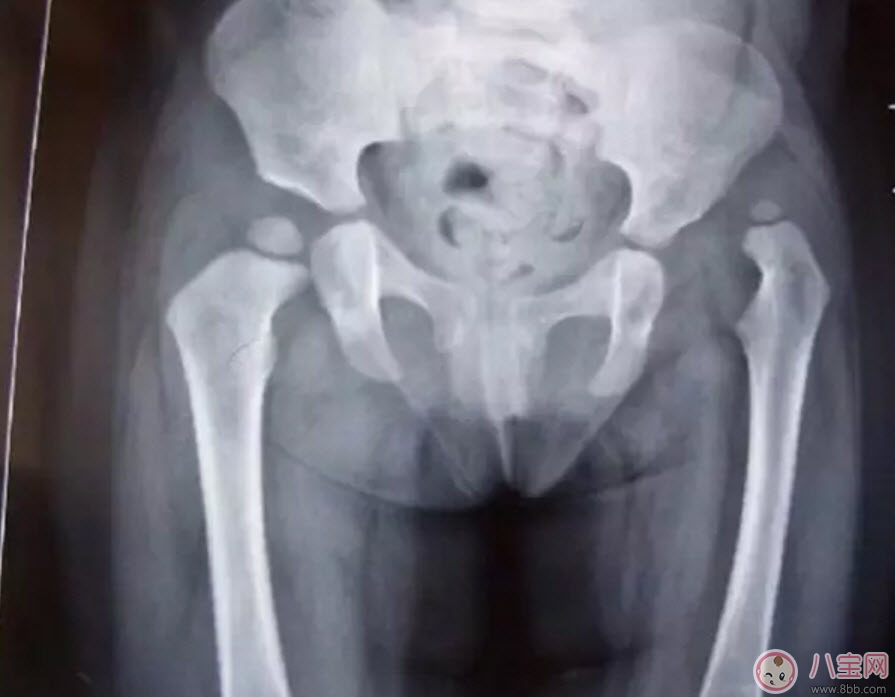

這是一個(gè)左側(cè)髖關(guān)節(jié)脫位的孩子的X光片。從這張片子上我們可以看到,孩子右側(cè)的髖關(guān)節(jié)是正常的,股骨頭和關(guān)節(jié)盂在一個(gè)水平位置上,但左側(cè)的股骨頭就完全離開了髖關(guān)節(jié)盂,跑到髖關(guān)節(jié)的上方去了,對于左側(cè)這種情況,我們就稱之為髖關(guān)節(jié)脫位。一般這種脫位都是先天的,或是孩子很小時(shí)候出現(xiàn)的,所以除了關(guān)節(jié)有脫位外,左側(cè)的股骨頭、股骨干、髖臼發(fā)育的也不正常,明顯比正常的一側(cè)要小。